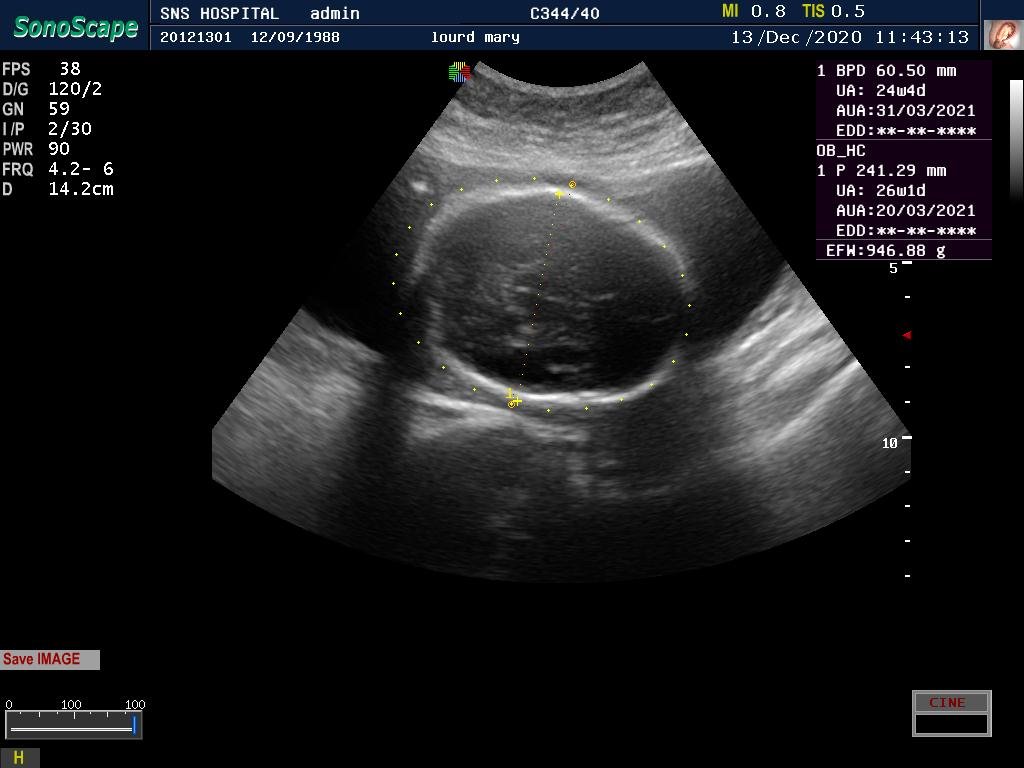

DIAGNOSIS – TYPE 2 DM ON INSULIN WITH INTRA UTERINE GROWTH RESTRICTION

32 yrs, MRS. M, G3P1L1A1 / LMP -03-06-2020 / EDD – 10-03-2021/ previous intrauterine growth restriction with a birth wt of 1.75kg.

Seen first time @ 18 weeks gestation in the month of October.

First visit U/s – 2+, hence was advised GTT., FBS-101 mg/dl, 1hour-206 mg/dl, 2hours-201mg/dl, patient started on INSULIN 5Iu-5Iu

The insulin requirement kept changing as the pregnancy advanced .she was already on aspirin and her uterine Doppler showed low resistance flow. Growth scan with Doppler every 4weeks done from 20 weeks.

There was growth lag of 2weeks @ 27 weeks gestation, Doppler U/A 50th percentile followed by growth scan every 2weeks with Doppler.

The parameters fell below 50th percentile but the interval growth was satisfactory.

Steroids completed @ 33weeks patient had PPROM @ 35 weeks, and delivered an alive preterm vaginal delivery – Boy, 2.2kg.